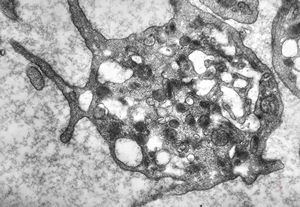

F,43y. | blood - leukemia - bacteriaemia - phagocytosed microbes

phagocytosed microbes

M,2w. | bacteriaemia - phagocytosed microbes

phagocytosed microbe